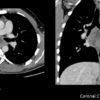

Lao hạch

Lao hạch - Ảnh 3

Lao hạch - Ảnh 4

» Thông tin: Nam giới – 27 tuổi.

» Lâm sàng: Đau ngực / Nuốt khó.